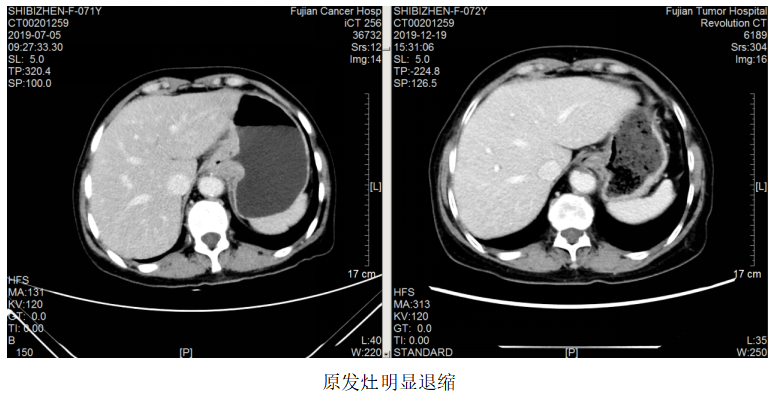

2021.5.18开始患者因经济原因改予汉曲优治疗至今,肿瘤进一步退缩,疗效评估PR。

该例患者为胃癌脑转移。脑转移患者的抗HER2治疗一直存在着大分子单抗和小分子TKI之争。有研究显示,由于脑肿瘤部位的血脑屏障受损,通透性要高于正常脑组织,因此曲妥珠单抗可以透过血脑屏障到达病灶部位,尤其是一些接受过脑放疗的病人更是如此。对这例患者,初诊时即存在脑转移,选择了曲妥珠单抗+化疗作为一线治疗,配合脑部放疗,达到PR效果,而后新增脑转移灶,再次放疗,继续曲妥珠单抗治疗,仍达到PR效果,患者前期予赫赛汀,后期因经济原因改予汉曲优,肿瘤依然进一步控制,患者OS>28个月。

本案例中,患者因经济原因后续转换为曲妥珠单抗生物类似药汉曲优进行治疗,肿瘤进一步退缩,疗效评估PR,患者OS>28个月。曲妥珠单抗生物类似药已得到国内外指南的用药推荐。2020年《中国生物类似药专家共识》认可生物类似药的临床替代[6]。2022年CSCO-GC指南指出生物类似药可以作为曲妥珠单抗的合适替代[7]。本案例也证实了汉曲优联合化疗在HER2阳性胃癌伴脑转移治疗上疗效显著,生物类似药与原研疗效等同,临床可以安心使用。